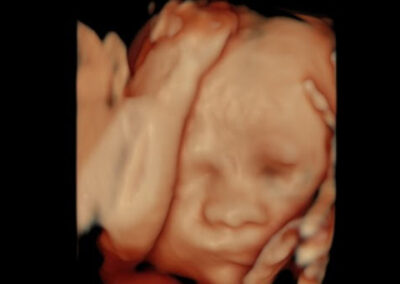

גלריה